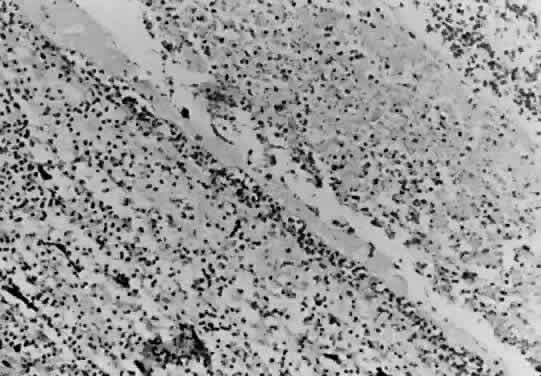

Bradyzoites are slowly metabolizing organisms found in cysts formed within the tissue of the infected host. The size of the Toxoplasma cyst varies, depending on the number of organisms that have multiplied within it. The cyst may reach more than 100 μm in diameter and may contain from 50 to 3000 organisms. The cyst wall is strongly argyrophilic and periodic acid-Schiff positive. It contains constituents that are derived from both the parasite and the host tissue. Constituent from the host tissue compose the outer part of the cyst, whereas those derived from the parasite are in the inner part of the cyst wall. Toxoplasmosis may be found in the inner layers of the retina after episodes of acute retinochoroiditis. The cyst may stay in the retinal tissue for years without showing any signs of invasiveness. Considering that the tissue cyst incorporates elements derived from the host into its outer wall, it is easily tolerated by the host, and no inflammatory reaction is seen around it (Fig. 2). It may remain for years in certain tissues, such as the eye or muscles, without provoking any inflammatory reactions. The bradyzoite inside the cyst derives its nutrition from the slow diffusion of substances through the cyst wall. The number of organisms increases within the cyst in the retina, and once the cyst wall breaks down by mechanical stretching, the bradyzoites escape, convert into tachyzoites, and invade contiguous cells. This process may lead to recurrence of retinitis. Certain immunologic mechanisms of the host may influence the organisms significantly. Immunosuppression coinciding with the rupture of the cyst and release of bradyzoites allows the organisms to become tachyzoites and proliferate in host tissue without restriction. The cyst of the Toxoplasma organism appears to be a defensive stage in its life cycle. The resistance of toxoplasmosis within chronically infected tissues of animals may lead to transmission of the disease by the ingestion of undercooked meat, including mutton, beef, pork, and chicken. Tissue cysts can develop within any organ and are commonly found in infected tissues of brain, eye, heart, skeletal muscles, and lymph nodes. Rupture of tissue cysts causes reactivation of the systemic toxoplasmosis in immune deficiency states, leading to dissemination of Toxoplasma organisms to other organs.

When the parasite attains intracellular habitat, it starts to multiply, leading to host cell destruction and release of live protozoa. Live organisms do not stimulate respiratory burst during phagocytosis, but heat-killed or antibody-coated organisms generate a respiratory burst by the macrophage. The parasite may retain some of the disrupted macrophage plasmalemma adherent to the surface immediately after invasion. A vacuole quickly forms around the parasite that has invaded the host cell. The parasitophore appears to be larger than the organism, with tubules connecting membrane with the plasmalemma of the parasite. Each vacuole contains one parasite, and several organisms may be seen within a single macrophage. The Toxoplasma organism has a remarkable ability to evade the respiratory burst of macrophages by remaining within the vacuole. In activated macrophages, however, the organism has difficulty surviving within the macrophage, and the parasite is killed after fusion between the cell membrane and the internal limiting membrane of the vacuole. The organism is, in general, resistant to hydrogen peroxide, but it is susceptible to oxygen intermediates generated by the xanthine oxidase system.